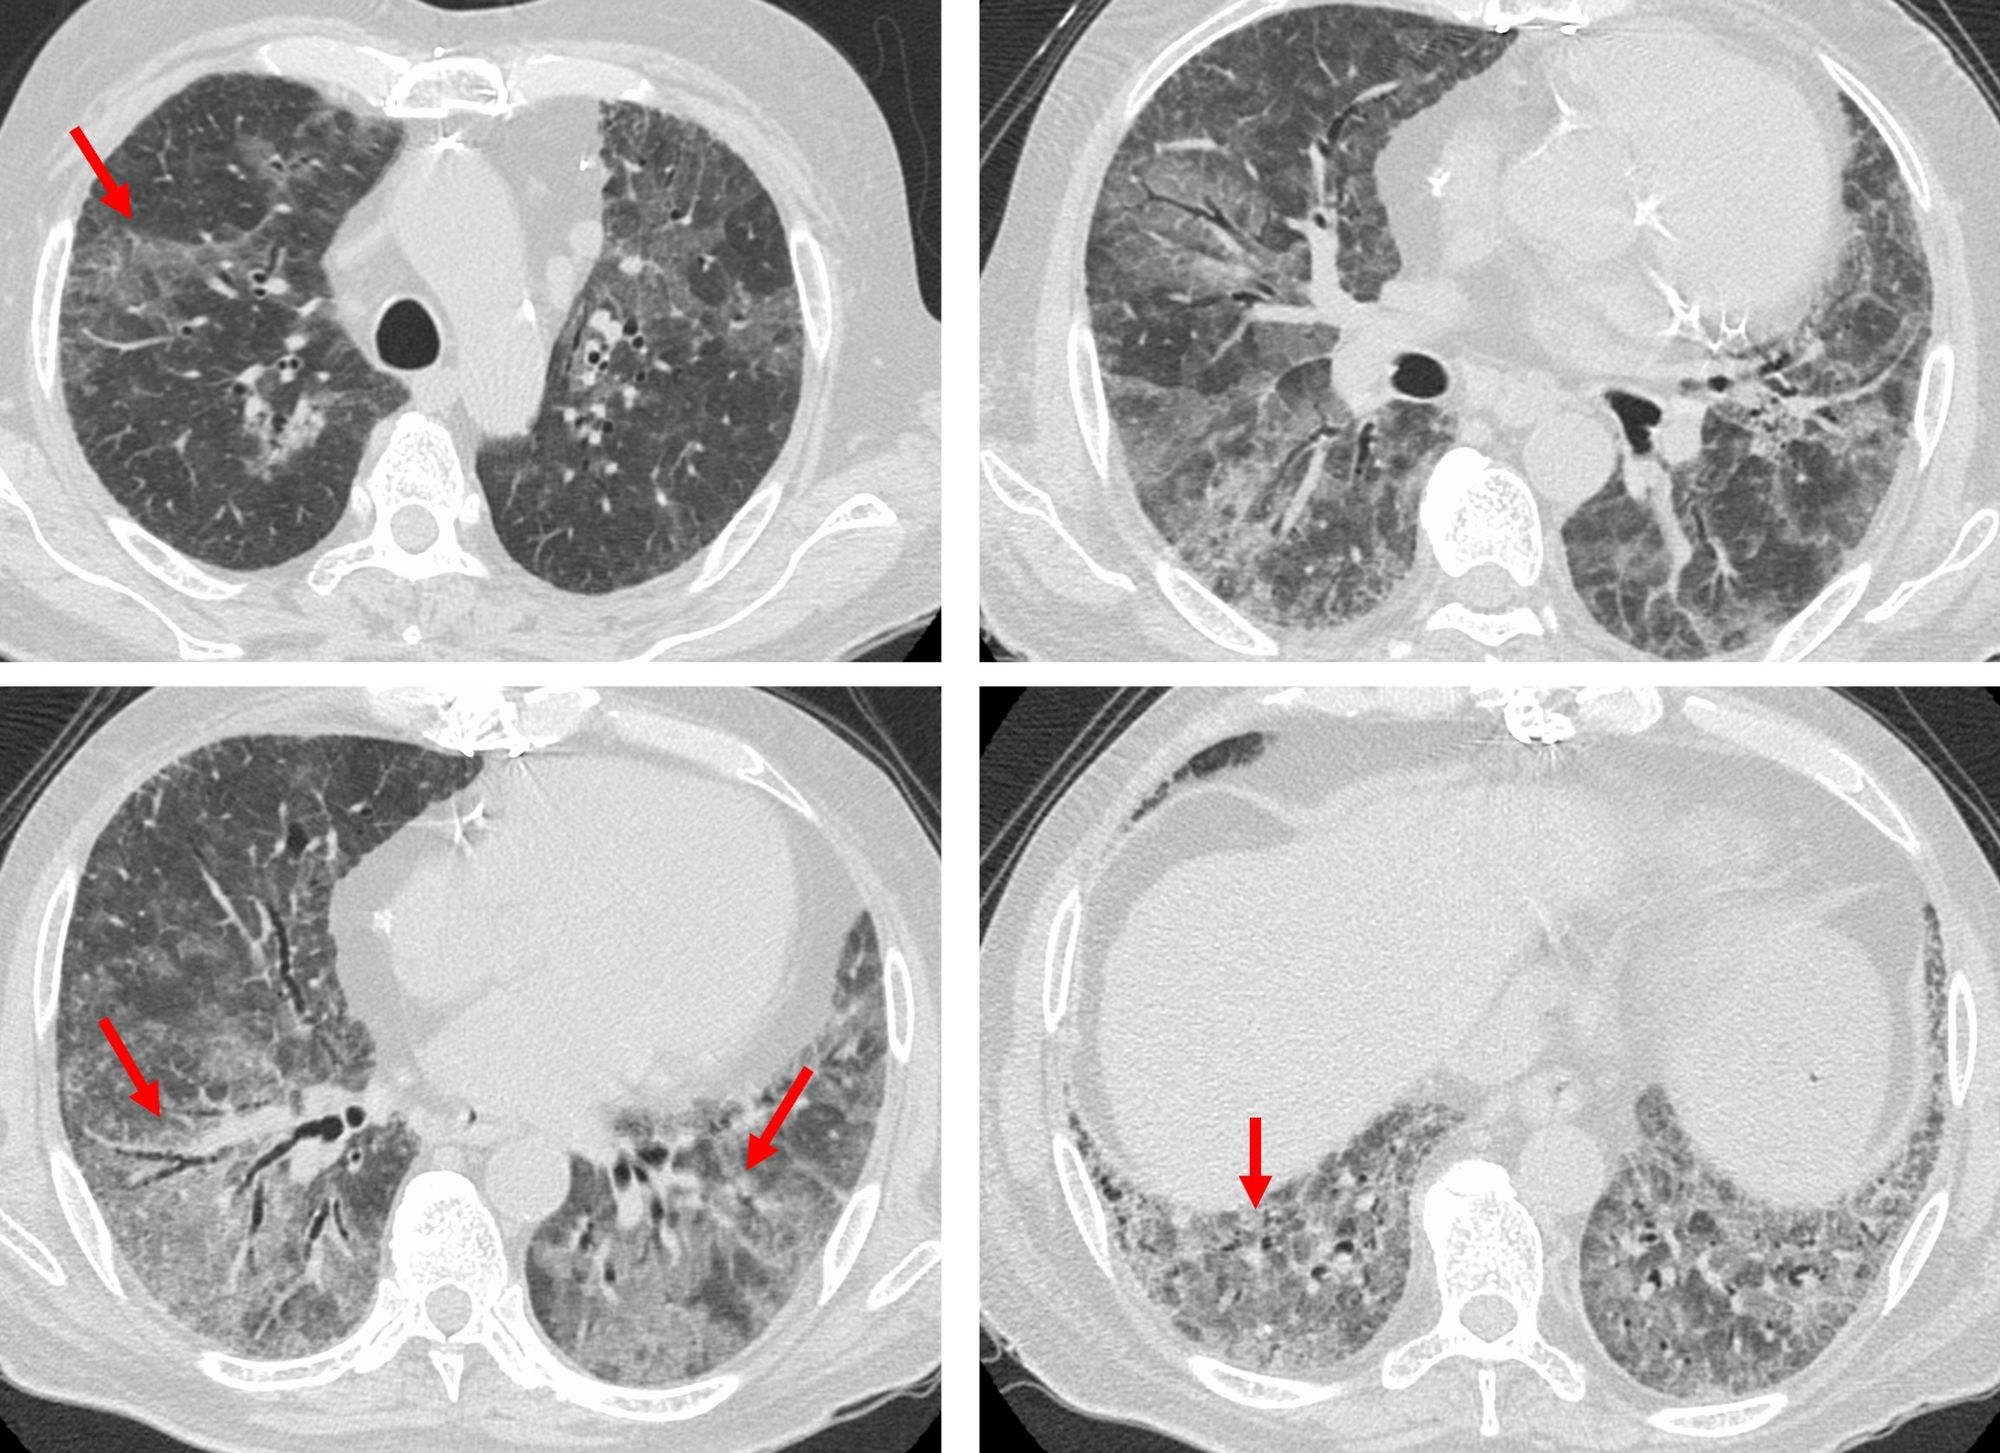

He then presented with acute onset worsening.

Thoughts?

- Acute exacerbation

- Infection

- Medication induced pulmonary injury

- Cardiac failure